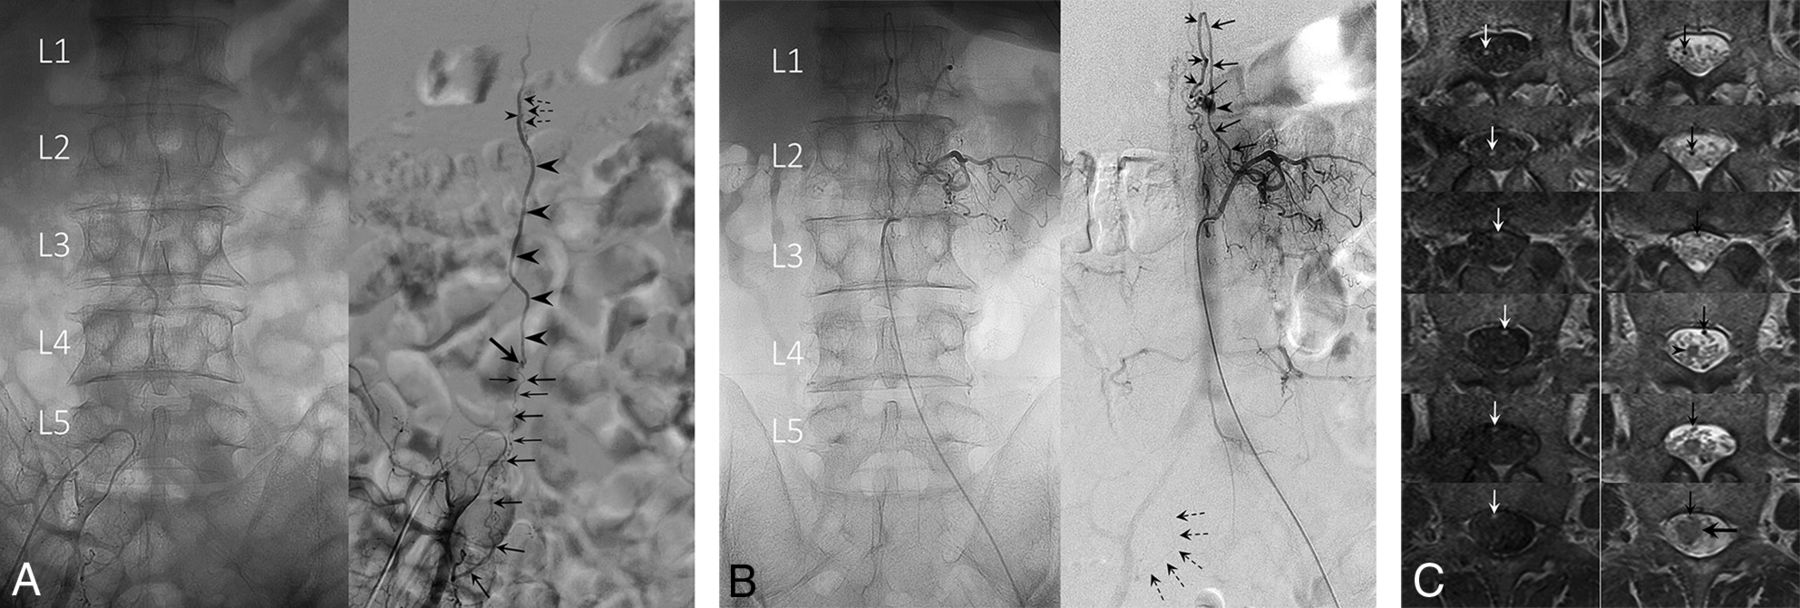

A, Angiogram of the left L1 lumbar artery in anteroposterior projection demonstrates a filum terminale AVF at the L4 level. The fistula (oblique arrow) is supplied by the caudal extension of the anterior spinal artery, which is the artery of the filum, and drained by the vein of the filum. The ASA does not change its course or caliber at the conus medullaris and maintains its robust caliber down to the fistula site. Note the parallel feeder and drainer pattern. B, Serial thin-section gadolinium enhanced T1WI (left column) and T2WI (right column) arranged in caudal (upper) to cranial (lower) order show the draining vein (arrows) merging with the spinal cord at the apex of the edematous conus medullaris (arrowhead). This finding suggests that this is the vein of FT.

A, Unsubtracted (left) and subtracted (right) angiograms of the right internal iliac artery. A radicular artery (large arrows) originating from the right S1 lateral sacral artery forms a fistula (oblique arrow) at the L4 level. Note a second small feeder contributing to the fistula (small arrows). The straight ascending draining vein (arrowheads) opens into the perimedullary vein at the L1 level (small arrowhead), demonstrated by the opacification of superficial pial veins (dashed arrows). This finding suggests that the draining vein is a radicular vein. The ASA had no contribution to the fistula (not shown). B, A coexisting L1 level perimedullary AVF supplied from the left L2 radiculopial artery (arrows). An aneurysm (arrowhead) is seen at the fistulous site (small arrow). Note the faint opacification of the right S1 lateral sacral artery, identical to that seen in A, supplying the L4 level fistula (dashed arrows). Note the descending, then ascending draining vein that is separate from the right S1 radicular AVF. C, Serial thin-section gadolinium-enhanced T1WI (left column) and T2WI (right column) arranged in caudal (upper) to cranial (lower) order show the draining vein (arrows) is off the cord at the apex of the conus medullaris (arrowhead). The draining vein eventually merges with the spinal cord at a higher level (large horizontal arrow). This finding suggests that the draining vein is a radicular vein.